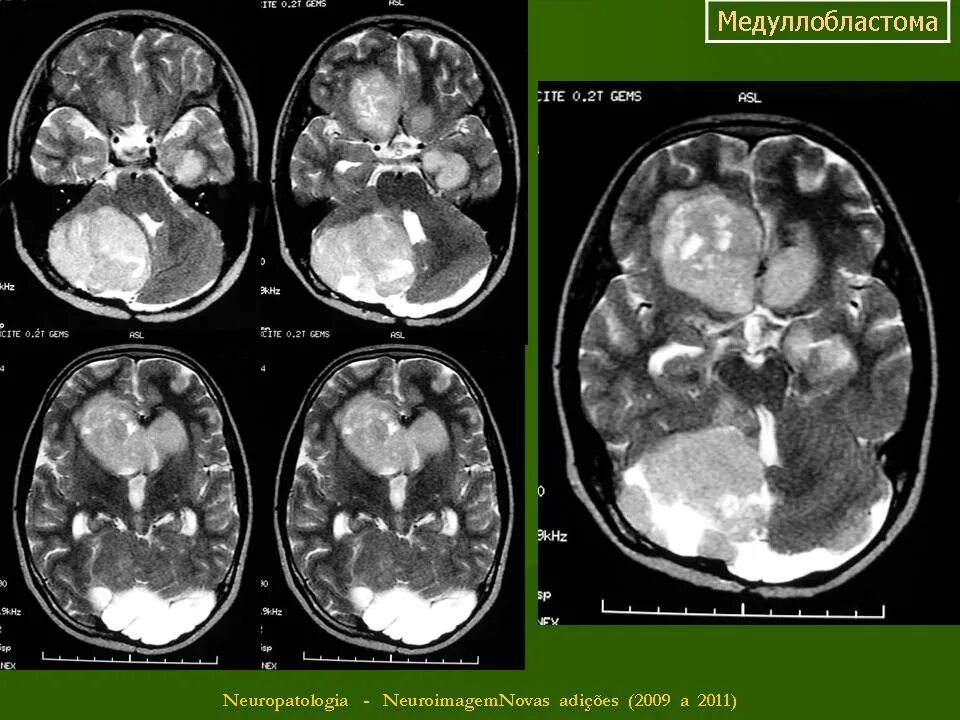

Медуллобластома это